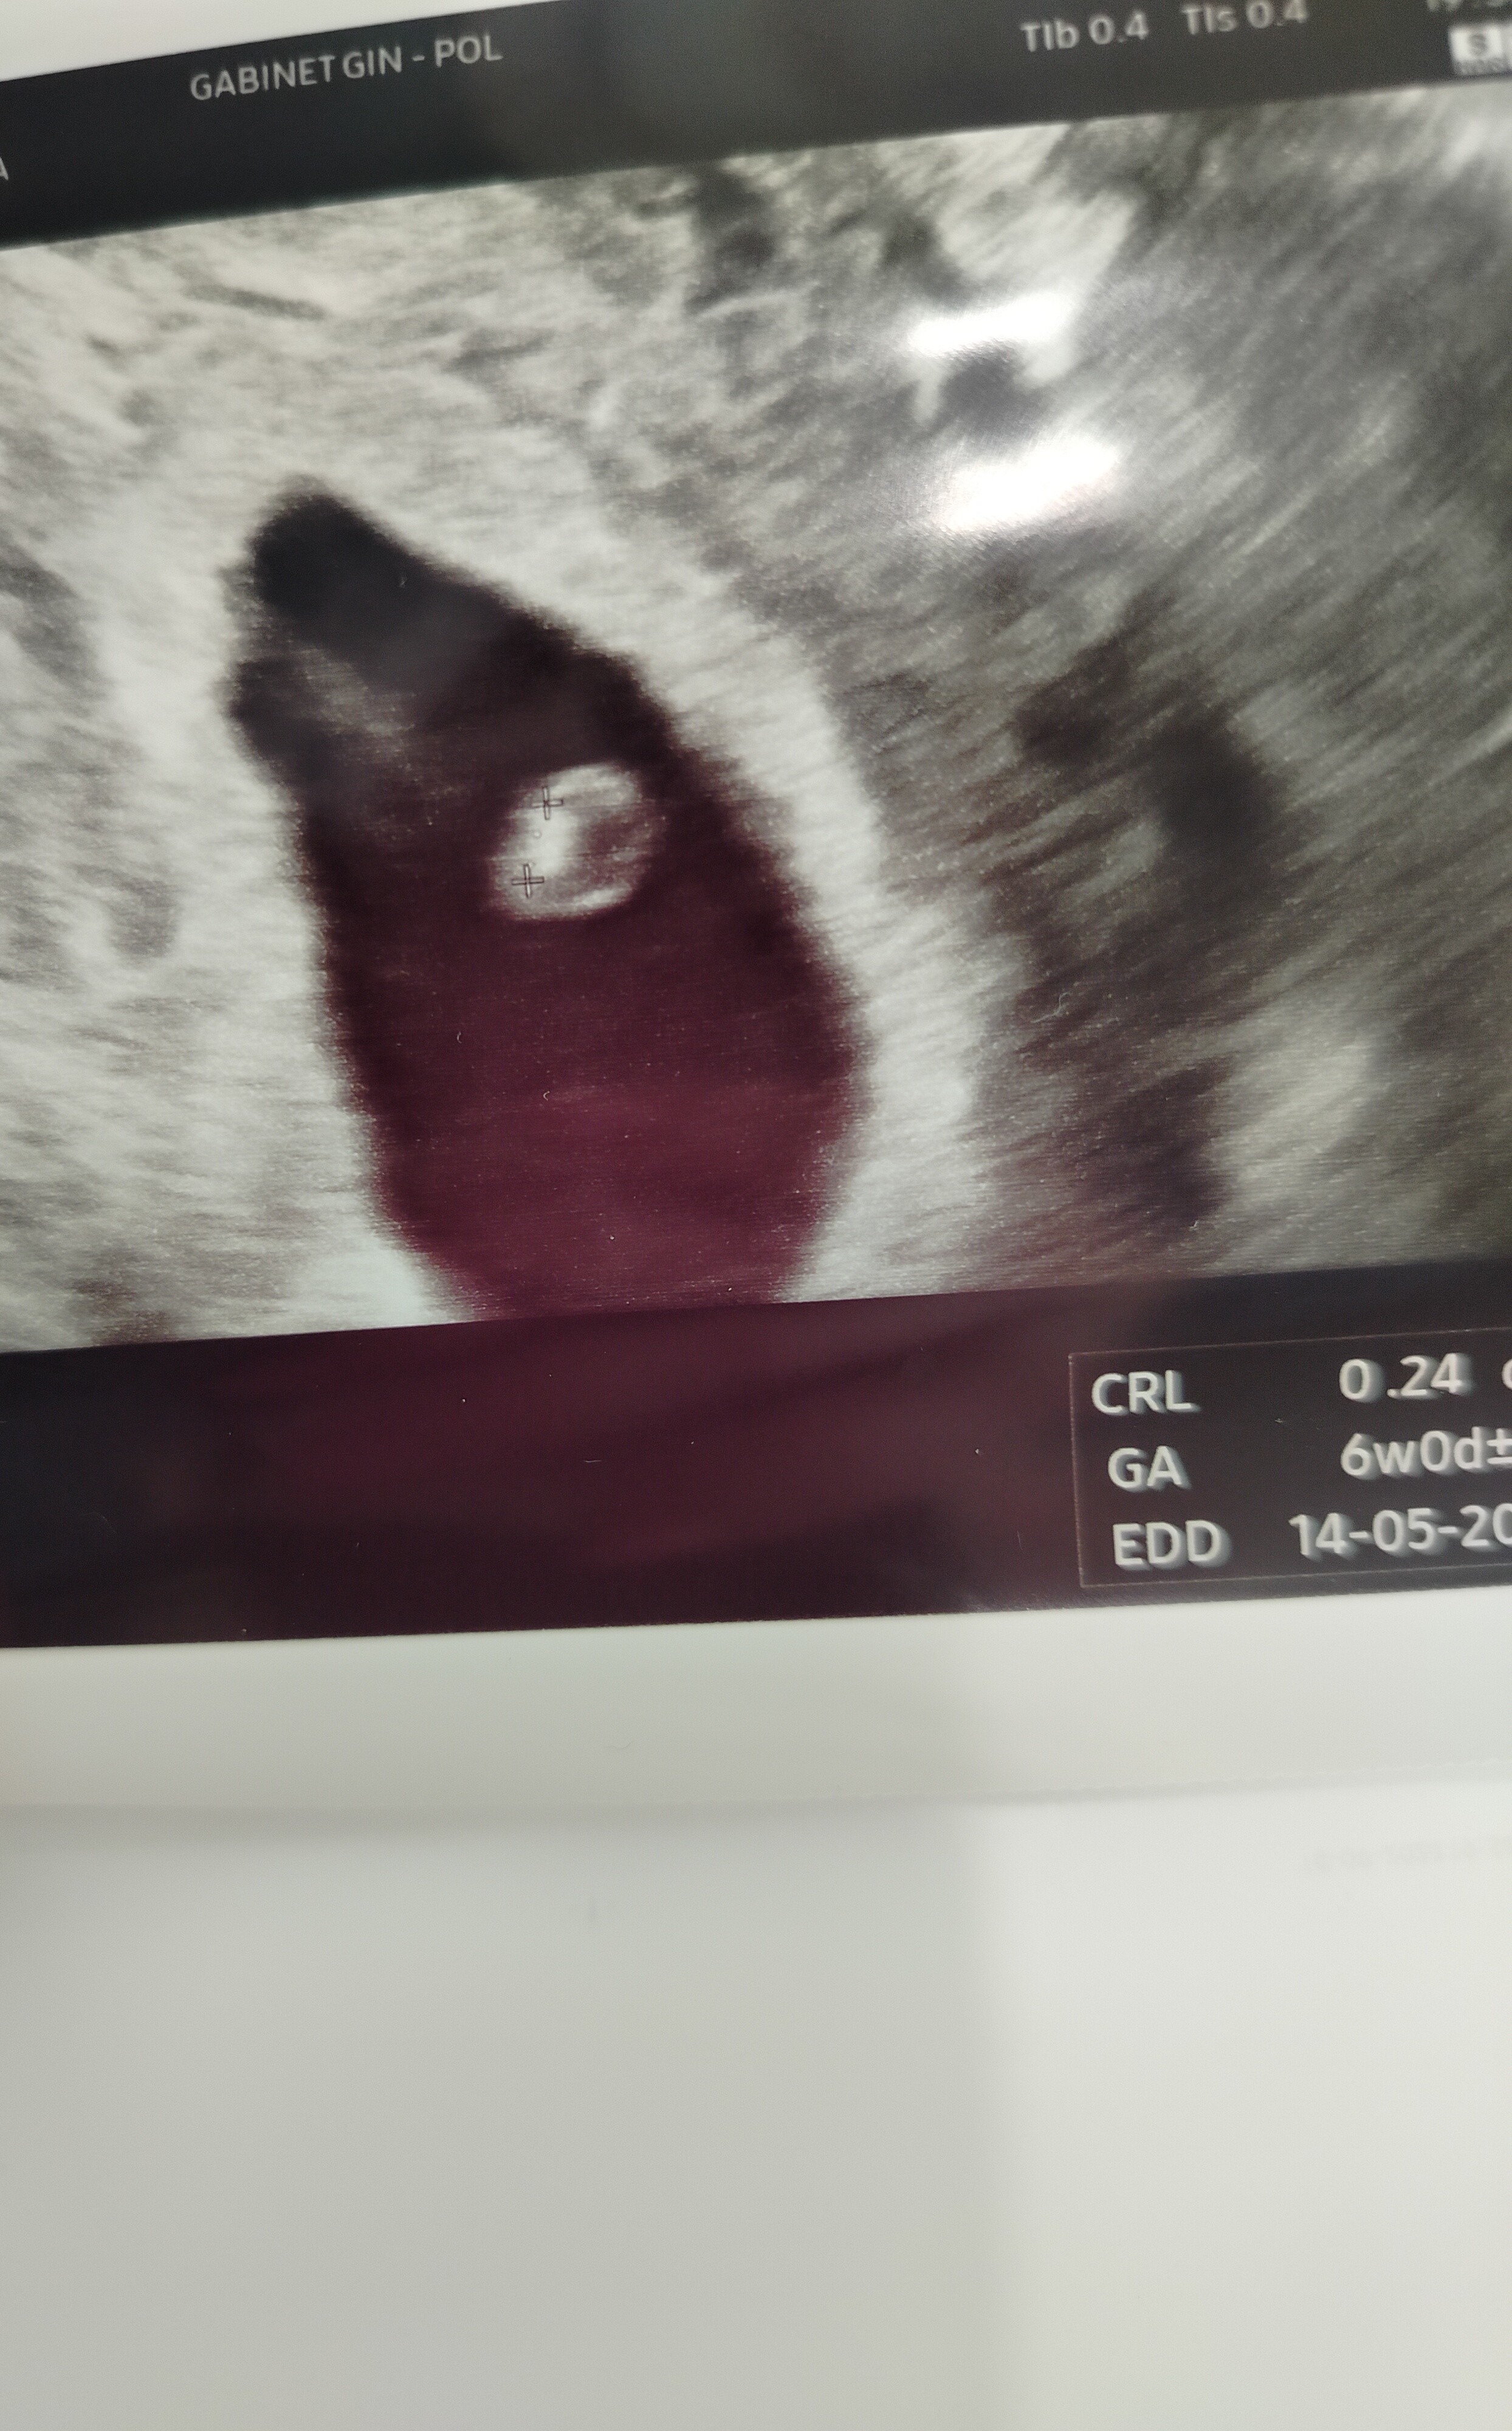

Dobra pisze bo wczoraj cały dzień poza domem a u lekarza obsuwa 40 min więc do gabinetu weszłam przed 20.00. ogólnie to jak na ten moment ok jest, tylko nie dopytywałam z serduchen bo było tylko powiedział lekarz że musi się wzmocnić. 😒 Wczoraj było 5+6. Mam wizytę u drugiego lekarza we wtorek więc zobaczymy co on powie a to moj Bąbel

Dobra pisze bo wczoraj cały dzień poza domem a u lekarza obsuwa 40 min więc do gabinetu weszłam przed 20.00. ogólnie to jak na ten moment ok jest, tylko nie dopytywałam z serduchen bo było tylko powiedział lekarz że musi się wzmocnić. 😒 Wczoraj było 5+6. Mam wizytę u drugiego lekarza we wtorek więc zobaczymy co on powie a to moj BąbelZobacz załącznik 1662188

Super! Piękny bąbelek! To w następnym tygodniu już powinno być serduszko :)